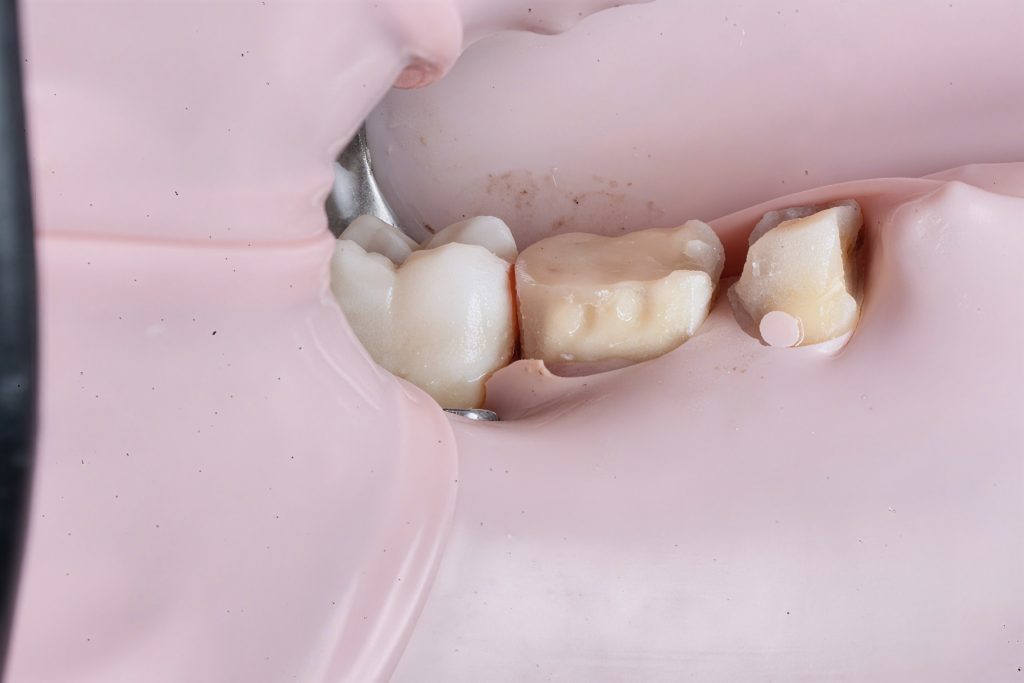

7️⃣ Cuspal Coverage Restoration

Cuspal anatomy reconstructed using Tokuyama Estelite Sigma Quick (A2). Incremental layering with cusp-by-cusp build-up reproduced occlusal morphology and controlled shrinkage. Each increment light-cured for 40 s under microscope visualization (Fig 7).

- Fig 7: Cuspal build-up with Tokuyama Estelite Sigma Quick.